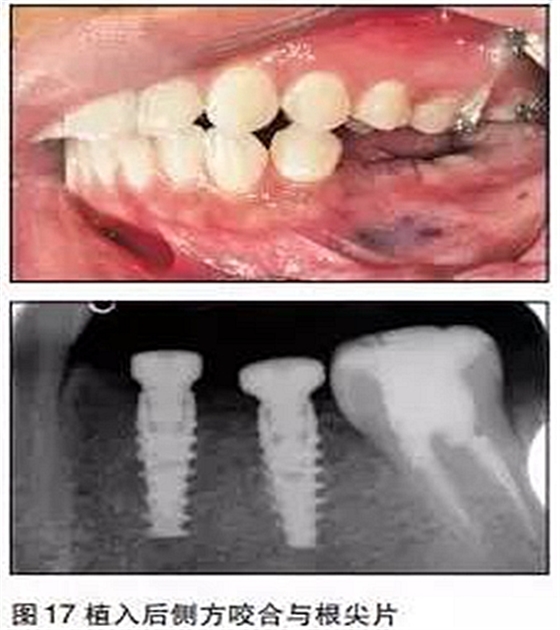

③用骨鑿去除部分牙槽嵴頂骨質(zhì),球鉆定位,逐級(jí)備洞,植入2枚NobelActivie4.3×10mm種植體,植體植入初期穩(wěn)定性35N;

④上愈合基臺(tái),一期縫合。

三個(gè)月后

采用閉口印模法取模,比色,送技工中心制作。

口內(nèi)就位

最后修復(fù)體在口內(nèi)就位,35N鎖緊螺絲,封閉螺絲口,納米樹脂充填螺絲開(kāi)口,調(diào)牙合,拋光完成。